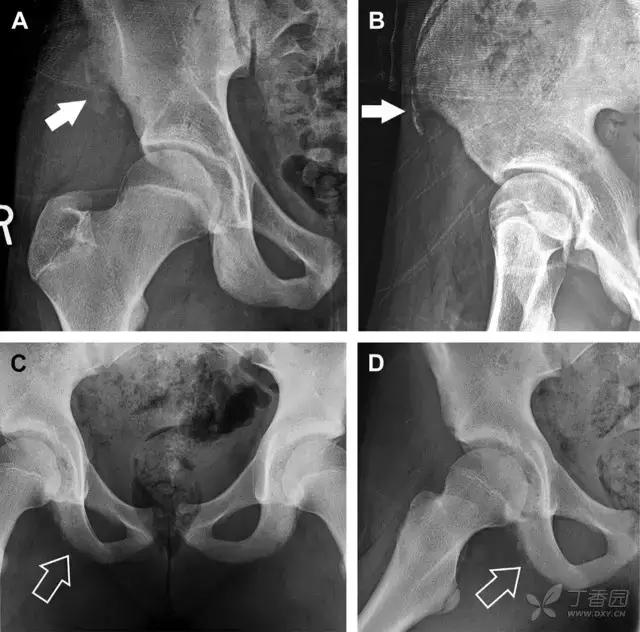

具有持续损伤因素的耻骨支骨折,可能看似轻微,尤其是合并骨质疏松的患者。因此,特别需要注意皮质缺损和骨密度改变。长跑运动员易发生耻骨应力性骨折,常常发生在靠近耻骨联合的下支。由于这些骨折为非移位骨折,所以常常被忽视。

图 3 自行车事故患者,侧方受力的髋臼前柱/耻骨骨折。A 正位平片示右侧髂耻线轻微中断(实箭头),此处异常最初并未发现。此外,右下方其实还有一处轻微耻骨支骨折(空箭头)。B 10 天后行骨闪烁显像证实了髋臼前柱骨折和侧耻骨下支骨折(箭头)。值得注意的是,左侧前柱亦存在异常

撕脱性骨折常在体育运动时由于肌肉强烈收缩引起。图 4 为容易发生儿童撕脱性骨折的部位。

图 5 儿童撕脱性骨折。正位片(A)和斜位片(B)示从髂前上棘撕脱的骨折碎片(箭头)。正位片(C)和另一个患者的蛙式位片(D)示右侧坐骨支皮质毛糙,腘绳肌腱撕脱损伤(如 C 和 D 空箭头所示)